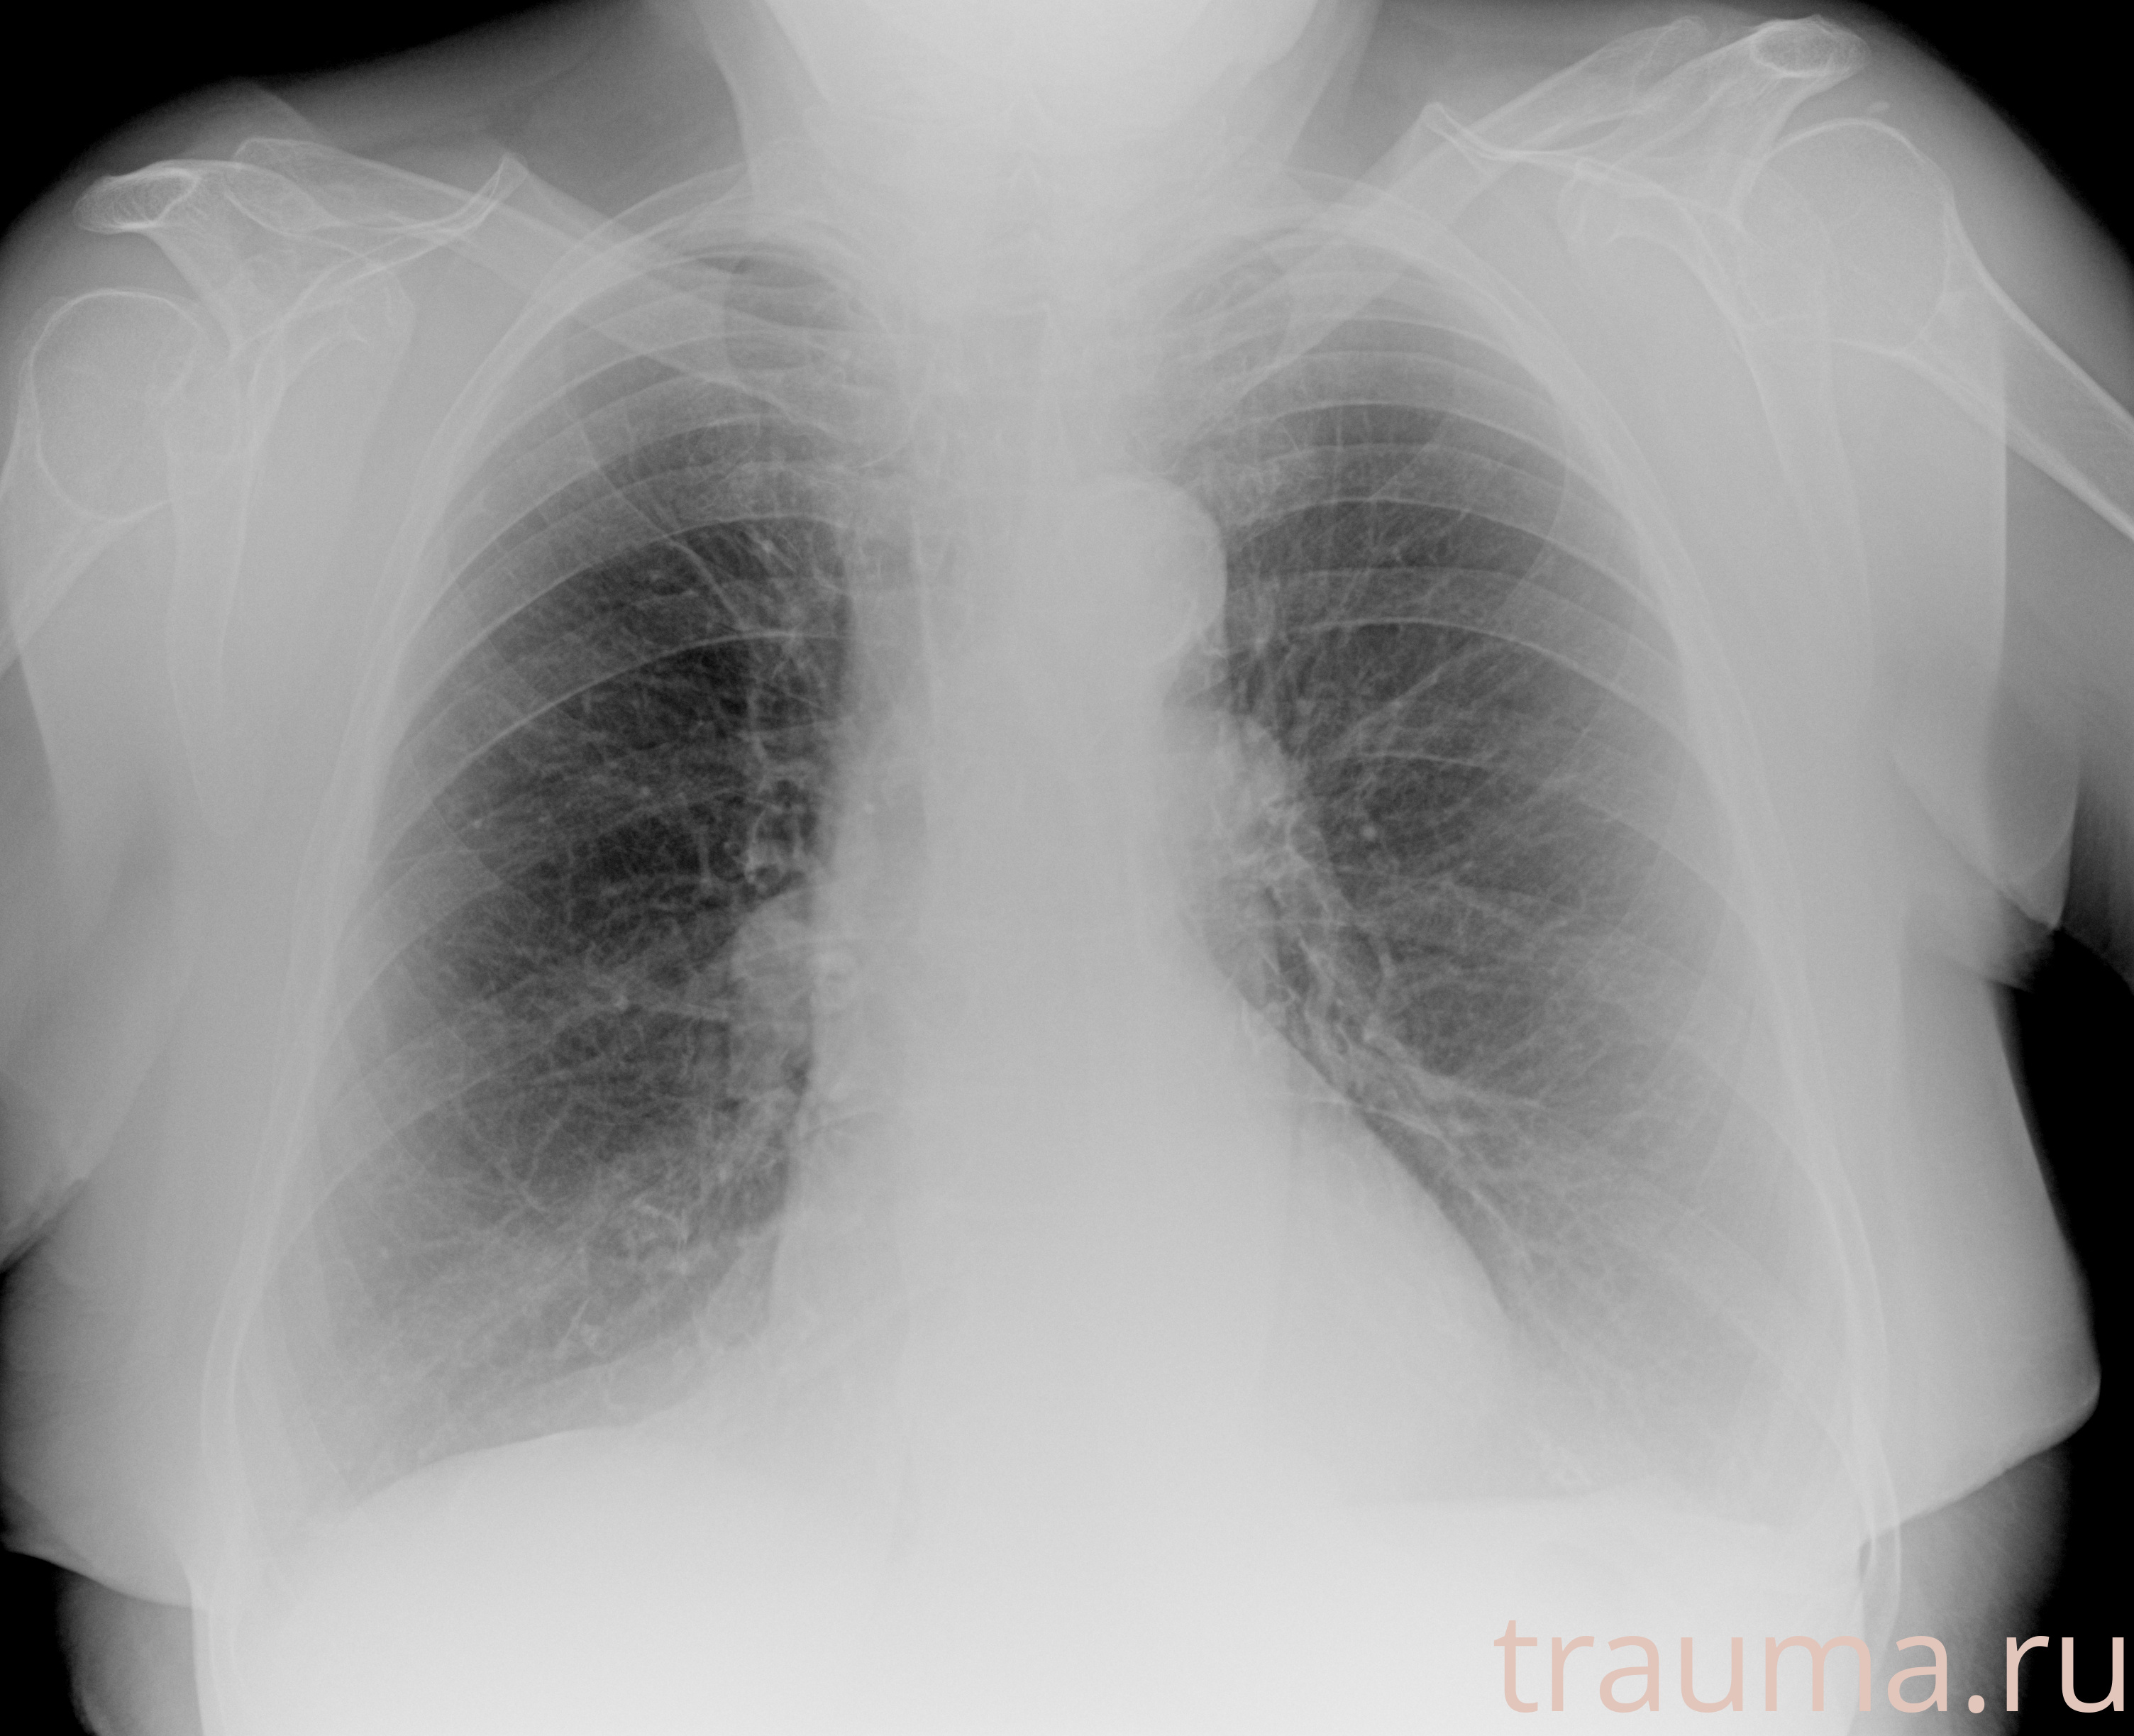

Рентгенограммы

Рентген на дому: по вашему адресу приезжает врач-рентгенолог, травматолог-ортопед с мобильным рентгеновским аппаратом, проводит диагностику травмы или заболевания, делает необходимые рентгенограммы, дает рекомендации по дальнейшему лечению. Получить качественные снимки в домашних условиях возможно благодаря уникальной методике, разработанной МосРентген Центром для института  Склифосовского

Яркость: 1   Контраст: 1   Инвертировать: 0 Увеличение: 1

Перетаскивайте мышь вверх/вниз для контраста, влево/право для яркости. Прокрутка колесом изменяет масштаб. Нажмите Сбросить для возврата к исходному изображению. При увеличении держите мышь в той области, которую хотите рассмотреть.